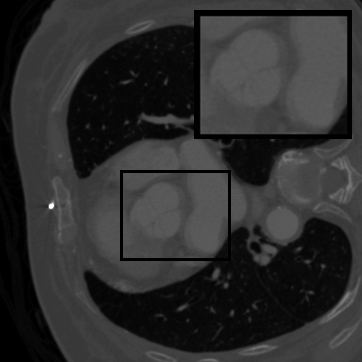

Figure 3: Visual comparison on TomoBank and LoDoPaB under random masking (ratio = 0.8). Rows 1 and 3 show the inpainted sinograms, while Rows 2 and 4 present the corresponding FBP [ramachandran1971three]-reconstructed images.

Table 1 summarizes the quantitative performance of FCDM and all baselines on the TomoBank and LoDoPaB datasets under both random and periodic masks. Figure 3 presents qualitative comparisons at a mask ratio of 0.8, showing both the inpainted sinograms and the reconstructed images obtained using FBP [ramachandran1971three]. Across all settings, FCDM consistently achieves the highest SSIM and PSNR values, demonstrating its strong capability in recovering structural details and suppressing noise-induced artifacts. Visual results in Figure 3 further confirm that FCDM produces smoother and more consistent sinograms, while other methods often exhibit angular streaking or local inconsistencies.